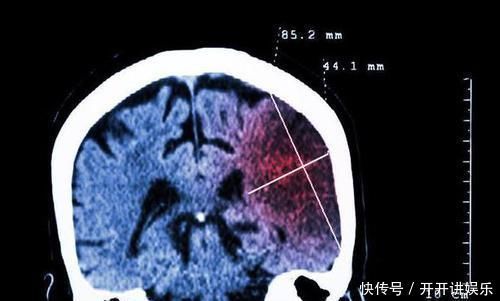

病例1:患者54岁中年女性,平时血压90/60mmHg,因为旅游劳累,旅途中血压飙升至140/90mmHg,患者头痛严重,当地医院未予降压治疗。3小时候出现喷射状呕吐,经过头颅CT正是发生了脑出血,紧急手术保住性命,但是留有严重后遗症。

病例2:患者56岁男性,平时血压150/100,口服降压药后可以达到130/85mmHg。因为工作压力大,情绪激动,导致血压飙升至220/110mmHg,仍然坚持工作一天。晚上经过急诊入院,给与静脉降压药紧急降压,同时后期经过调整,血压逐渐恢复正常。患者没有出现脑出血。

大家看,这两个患者,第二个病人比第一个病人血压是不是更高,可是为什么没有脑出血?而发生脑出血的是第一个血压偏低的患者?这就涉及到很多的问题。其实,脑出血的发生,必要因素里面,除了血压高以外,还要有一个病理基础。这种病理基础大部分人是动脉粥样硬化,有些人是先天畸形。只有全部因素都具备了,才会为脑出血创造发生的机会。